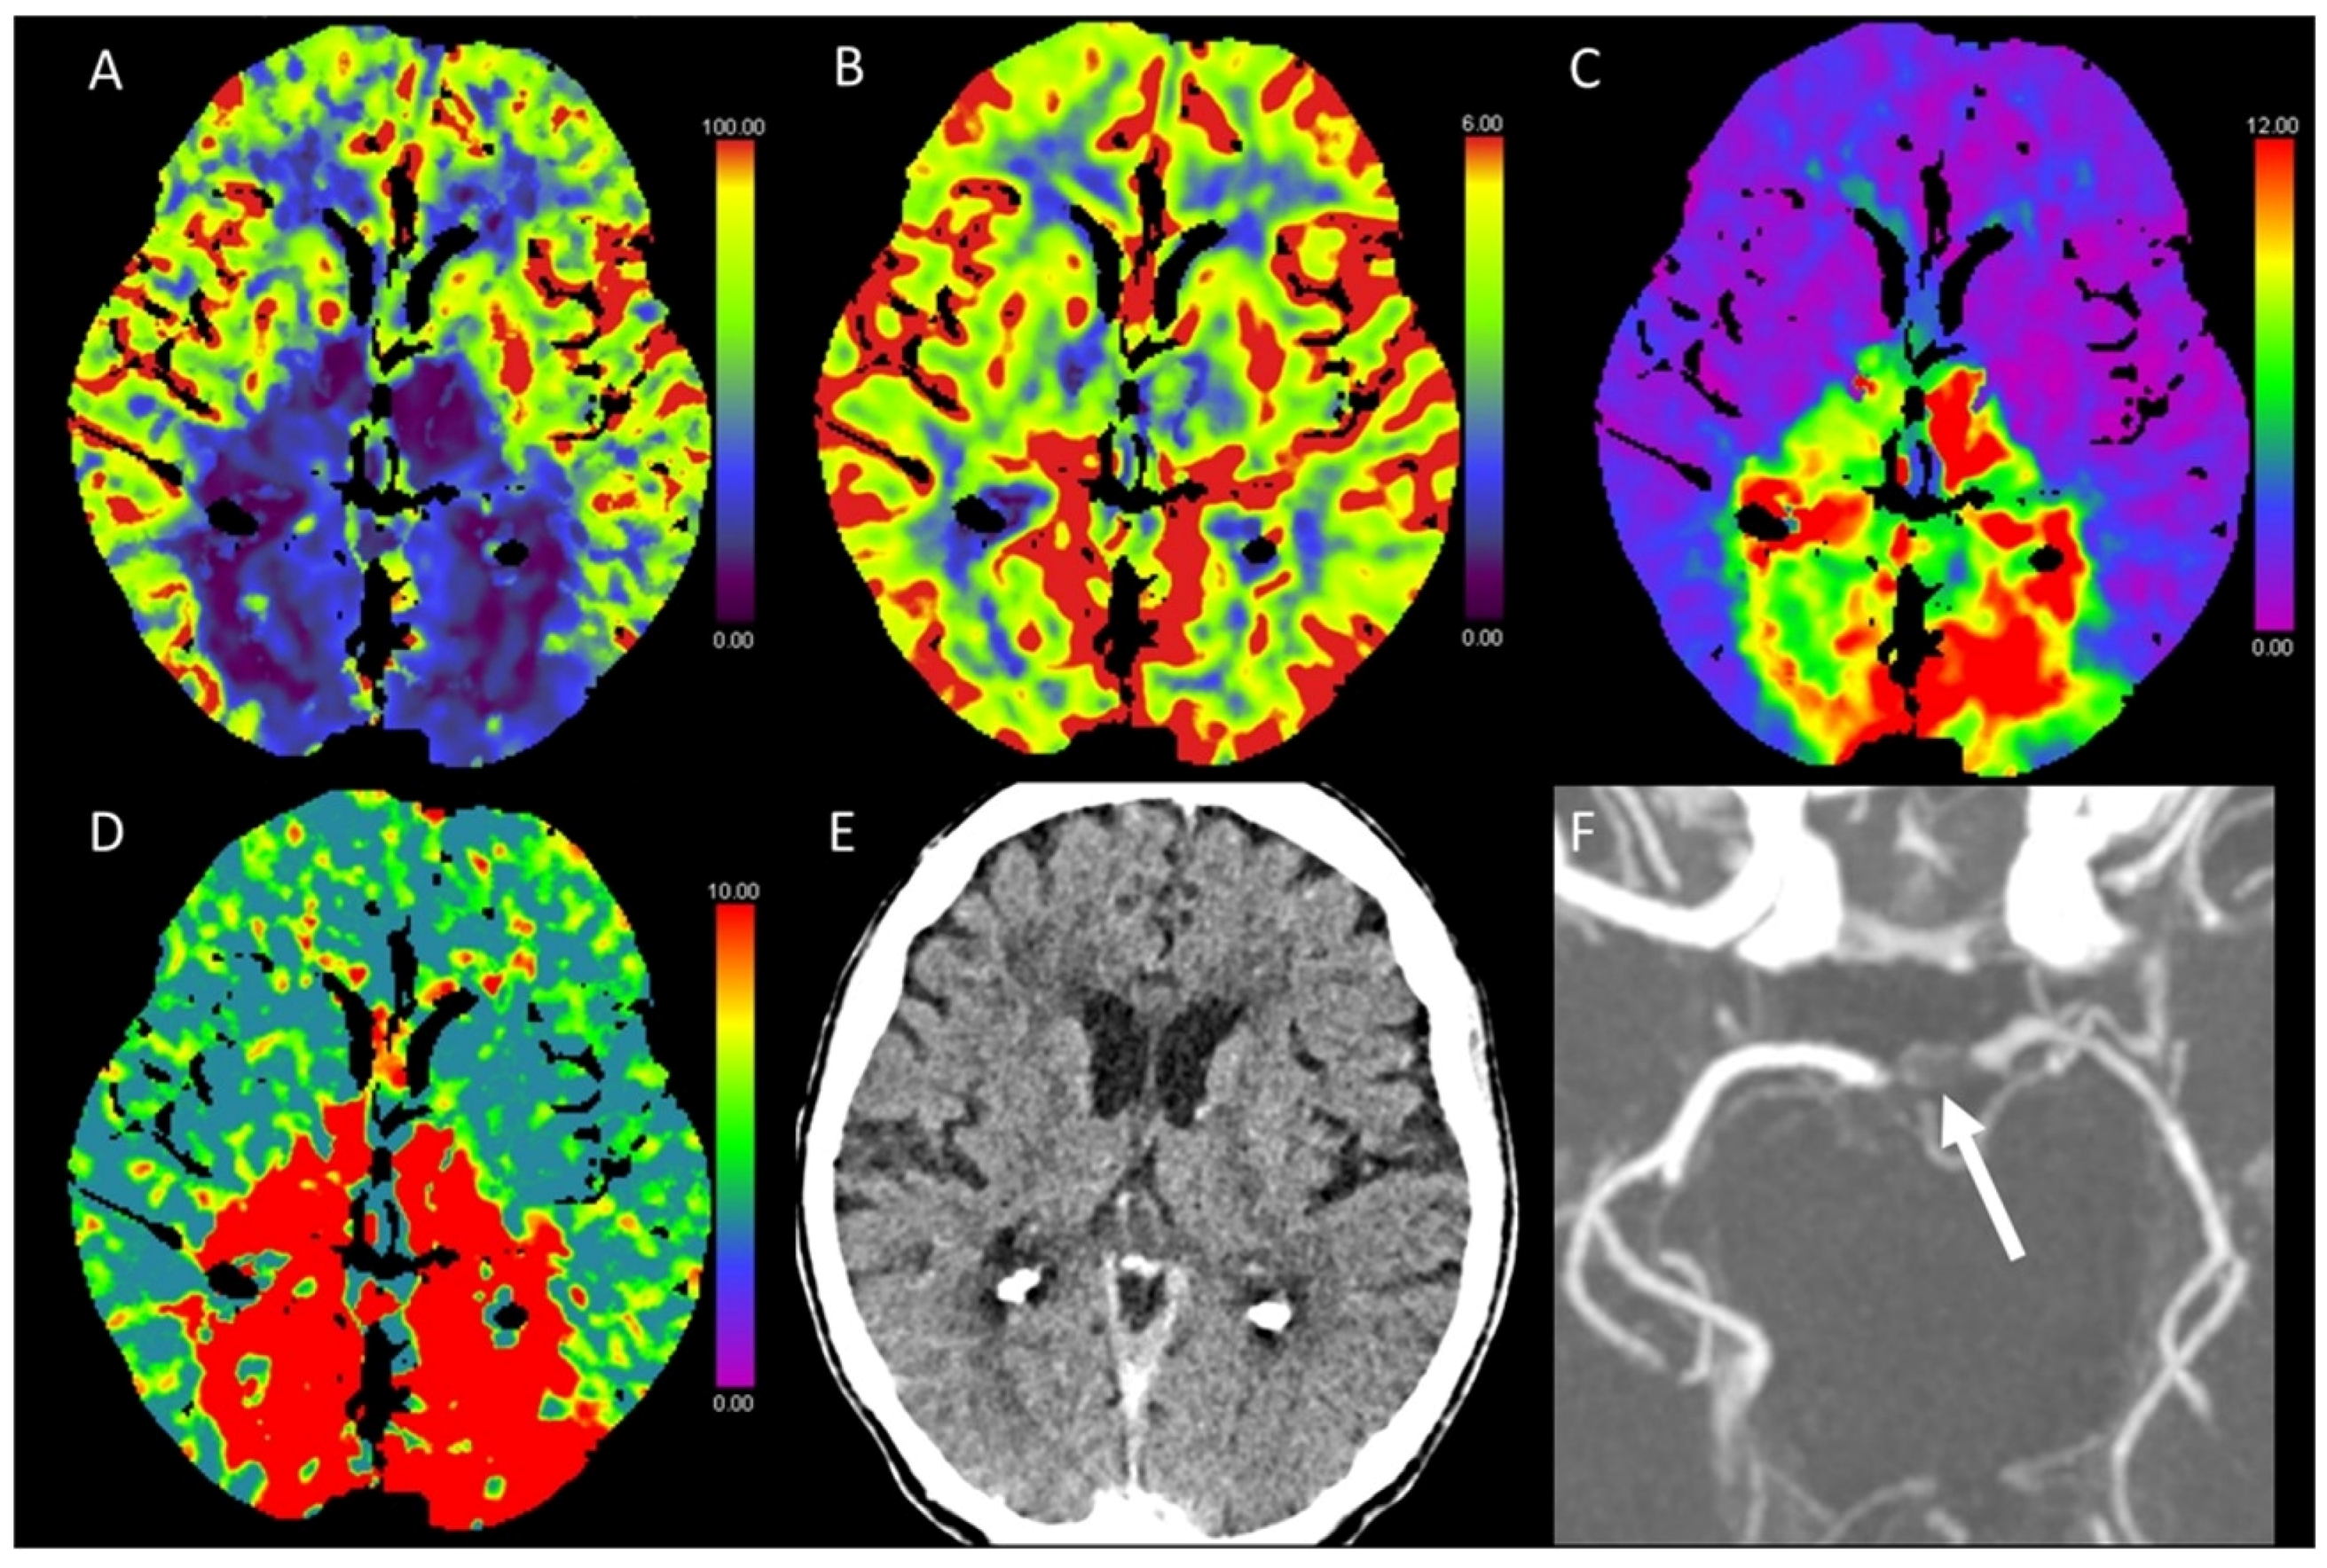

3.5. Hypotensive Cerebral Infarction (HCI) with Watershed Infarcts/Border Zones